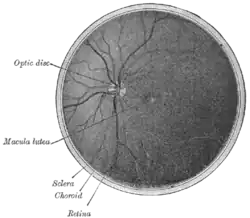

![]() Interior de la mitad posterior del globo ocular izquierdo. | ||

Irriga la retina.[1] La parte central de la retina donde los rayos de luz se enfocan tras pasar a través de la pupila y el cristalino es una zona circular denominada mácula. El centro de esta zona circular es la fóvea. La fóvea y una pequeña zona que la rodea no reciben sangre de la arteria central de la retina o de sus ramas, sino de la coroides en su lugar.

Si la arteria central de la retina se ocluye, se produce una pérdida completa de la visión en el ojo correspondiente. La retina al completo (con la excepción de la fóvea) se vuelve pálida, hinchada y opaca, mientras que la fóvea central aún aparece rojiza (esto se debe a que se transparenta el color de la coroides). Esta es la base de la famosa "mancha rojo cereza" que se ve en la retina en el examen del fondo de ojo cuando existe oclusión de la arteria central de la retina (OACR, o CRAO en inglés).